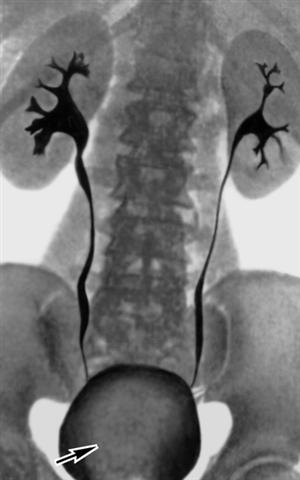

Рис. 3. Урограмма при злокачественной опухоли мочевого пузыря: виден дефект наполнения, обусловленный опухолью мочевого пузыря (указан стрелкой).